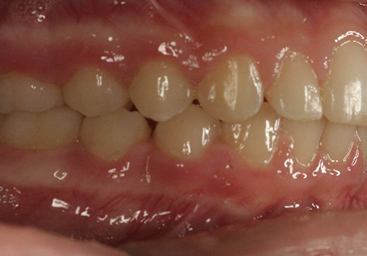

Crossbites are seen when the bottom teeth are further out relative to the top teeth. They can occur on front or back teeth and can lead to a number of problems including jaw pain and excessive wear of the teeth. This patient’s crossbite was on her right molar and was corrected with our ceramic braces. Sometimes, an expander is used to correct a crossbite if there are many teeth in crossbite.